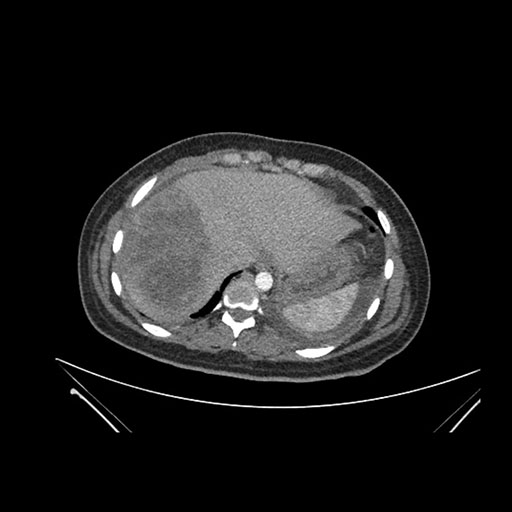

Axial Arterial